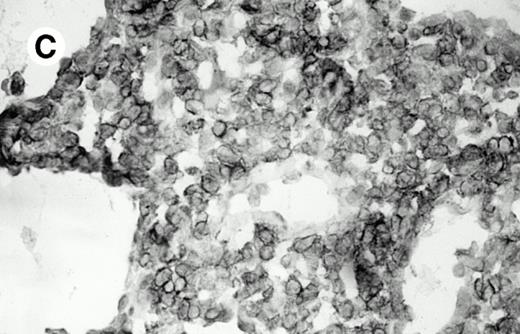

Three cases (cases no. 1 to 3) were located in the nasal cavity. The neoplastic infiltrate consisted of medium and/or large pleomorphic lymphoid cells (Fig 1)intermingled with variable numbers of small lymphoid cells, plasma cells, eosinophils, and histiocytes. Features of angiocentrism and angioinvasion, epitheliotropism, and areas of necrosis were observed in all three cases. Patient no. 4 presented with disease restricted to the lung and an open-lung biopsy was available. The neoplastic infiltrate was composed of large atypical lymphoid cells and was predominantly interstitial without extensive destruction of the normal architecture. Features of angiocentrism, angioinvasion, and epitheliotropism were present (Fig 2A and B). Case no. 5 involved the larynx, extending to the piriform sinus, the ventricle, and the arytenoid. One month later, the lymphoma disseminated to the subcutaneous tissue in the spinal region and biopsy specimens from both sites were available. The neoplastic cells were medium and large, with abundant clear cytoplasm and slightly irregular nuclei with dense chromatin. Epitheliotropism was present in the larynx mucosa. Small foci of necrosis and angiocentrism were seen without angioinvasion. Three patients presented with cutaneous disease. Cases no. 6 and 7 were comparable, as both histories started with necrotic subcutaneous nodules of the thigh, which on histologic analysis were characteristic of cytophagic histiocytic panniculitis without evidence of lymphoma (Fig 3A). Second excisional biopsies of cutaneous nodules obtained 7 and 5 months later, respectively, showed characteristic features of lymphoma in both cases (Fig 3B). However, in case no. 6, skin biopsy specimens showed an epidermotropic PML lymphoma extending to the dermis and the subcutaneous tissue, whereas in case no. 7, the neoplastic infiltrate consisted of a PSC confined to the subcutaneous tissue, admixed with benign histiocytes that showed phagocytosis. Patient no. 8 presented with recurrent skin lesions with spontaneous remission over a period of 10 years. The initial skin biopsies demonstrated an intense epidermotropic neoplastic infiltrate that extended to the superficial and deep dermis composed of atypical PML cells. All cutaneous cases displayed features of angiocentrism, but angioinvasion was observed only in case no. 6 and foci of necrosis in cases no. 6 and 8.

Subcutaneous γδ T-cell lymphoma (case no. 6). (A) Initial biopsy sample shows characteristic features of cytophagic histiocytic panniculitis without evidence of lymphoma cells; (B) second biopsy performed 7 months later demonstrates involvement of the subcutaneous tissue by a pleomorphic γδ T-cell lymphoma (hematoxylin-eosin stain).